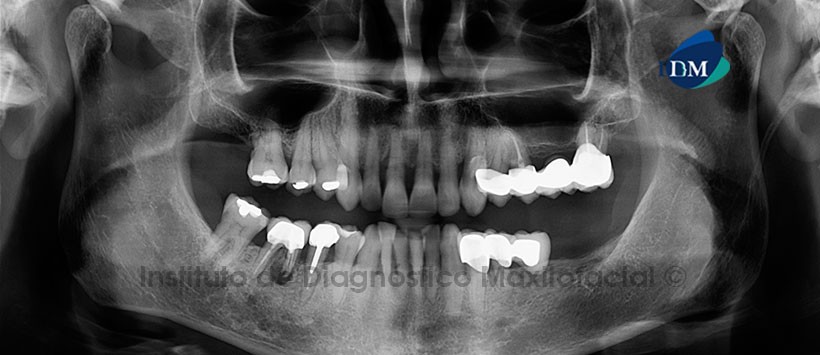

Paciente femenino de 62 años de edad acude al Instituto de Diagnostico Maxilofacial para evaluación general debido a que se le realizará una rehabilitación oral integral.

A la evaluación de la radiografía panorámica, observamos la mineralización del proceso estilohioideo de lado izquierdo, neumatización alveolar de ambos senos maxilares, reabsorción ósea severa del maxilar superior y ausencias de múltiples piezas dentarias. Siendo lo más resaltante la presencia de una imagen radiolúcida de forma circular localizada en la raíz mesial de la pieza 46 compatible con proceso osteolítico periapical y osteítis condensante circundante a la lesión, así mismo esta misma raíz cuenta con material de obturación de conductos subextendido y a su vez un trazo radiolucido en el tercio apical. (Figura 1)